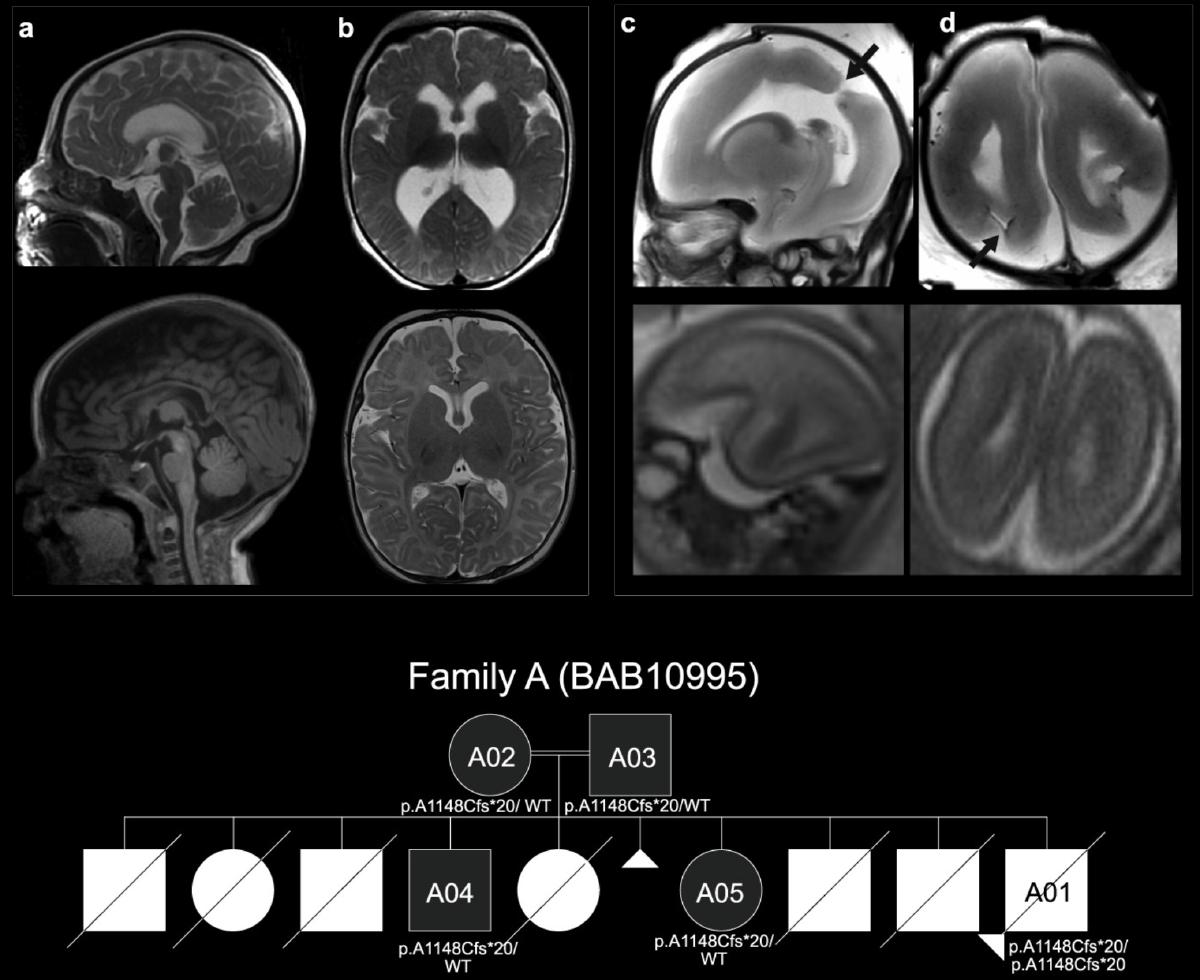

Loss of non-motor kinesin KIF26A causes congenital brain malformations via dysregulated neuronal migration and axonal growth as well as apoptosis

Qian X*, DeGennaro EM*, Talukdar M, Akula SK, Lai A, Shao DD, Gonzalez D, Marciano JH, Smith RS, Hylton NK, Yang E, Bazan JF, Barrett L, Yeh RC, Hill RS, Beck SG, Otani A, Angad J, Mitani T, Posey JE, Pehlivan D, Calame D, Aydin H, Yesilbas O, Parks KC, Argilli E, England E, Im K, Taranath A, Scott HS, Barnett CP, Arts P, Sherr EH, Lupski JR, Walsh CA

Dev Cell 2022 Read Article